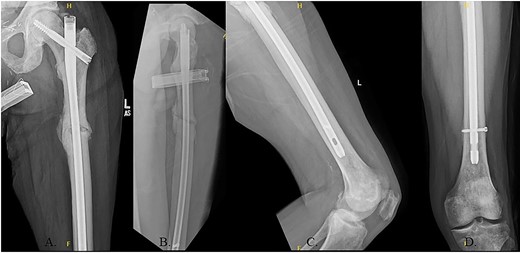

(A) AP radiograph of left hip with implant; (B) lateral radiograph of left hip with implant; (C) reduced fracture site with implant; (D) distal femur with implant.

The patient immediately was weight-bearing as tolerated to the operative extremity and worked with physical therapy (PT) to include 80 ft on post-operative day (POD) #2 with use of a front-wheeled walker. He continued to progress with PT and was discharged home POD #8 with home health/PT. At 12 months, the patient denied pain, and XRs demonstrated robust callus formation and bridging healing at the fracture site (Fig. 6).

(A) 12-month post-operative AP radiograph of left hip; (B) 12-month post-operative lateral radiograph of left hip; (C) 12-month post-operative lateral femur radiograph; (D) 12-month post-operative AP distal femur radiograph.